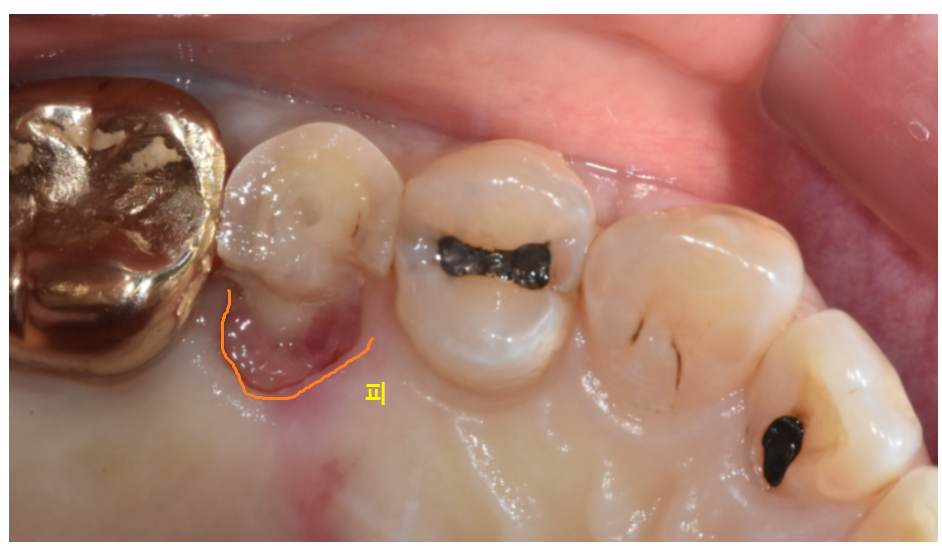

해당 환자분도 두번씩 뽄을 떠서 보냈는데...

(일반적으로는 1번만 뜨지만...

피나 침 등에 의해 뽄이 잘 안나오면

두세번씩 뜨기도 합니다ㅠㅠ)

처음 치료할 때 치아가 많이 떨어져나갔고

잇몸에 피가 나면서

나오지 않은 부분이 있었네요~

오차가 발생했습니다.